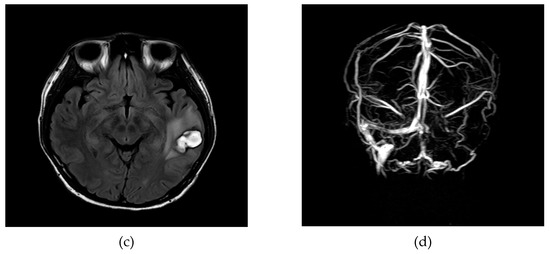

2. Case Report